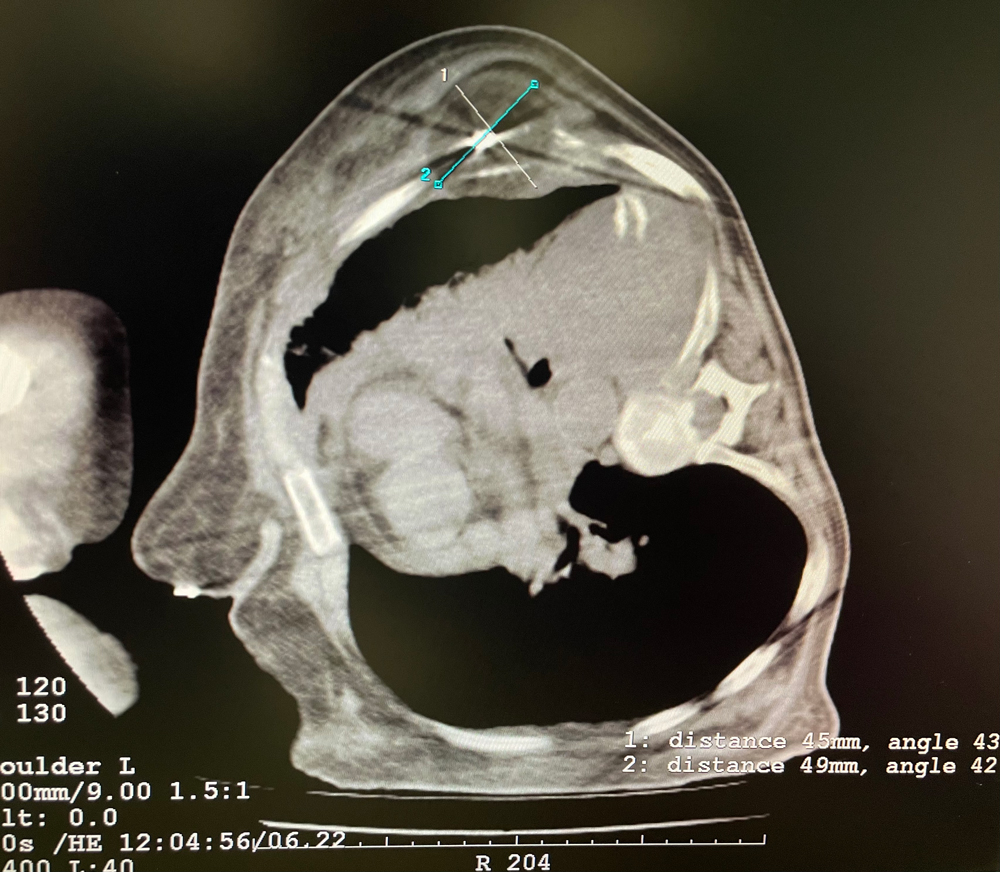

女,42歲,復發(fā)性脂肪瘤,病灶位于右側膝關(guān)節,直徑大小13cm。采用雙針?lè )桨?,共進(jìn)行6個(gè)凍融循環(huán),最大冰球直徑達8.2cm,術(shù)中多方位治療全面覆蓋病灶范圍。患者術(shù)后狀況良好。